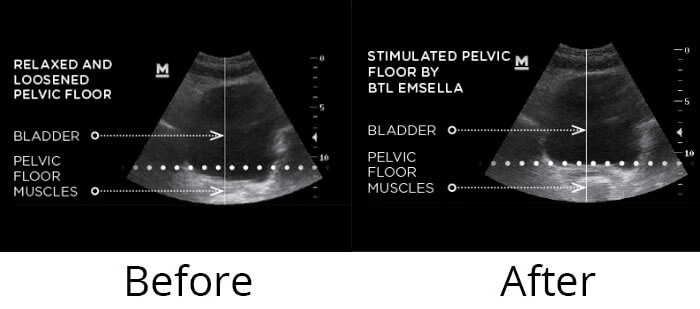

La Terapia Magnética Super Inductiva (SIS) o HIFEM es un tratamiento no invasivo que fortalece los músculos del suelo pélvico y mejora tu bienestar de manera segura y cómoda.

El suelo pélvico está formado por un grupo de músculos y tejidos que dan soporte a los órganos internos y son fundamentales para la estabilidad corporal, la continencia urinaria y la salud sexual.

Con el paso del tiempo, el embarazo, el parto o la menopausia, esta zona puede debilitarse y provocar problemas como pérdidas de orina, dolor pélvico, disfunciones sexuales, prolapsos o diástasis abdominal.

Tradicionalmente la recuperación dependía de ejercicios como los Kegel y de tratamientos de fisioterapia. Hoy existe una alternativa innovadora y cómoda: la Estimulación Magnética Funcional